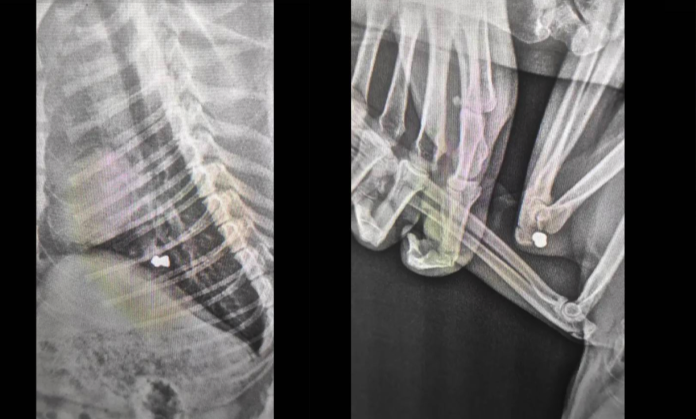

"Ось так виглядає Мурзай в середині.

Йому без жалю всадили дві кулі.

Зараз котик на огляді і підготовці до операції", - коментує фото авторка допису.